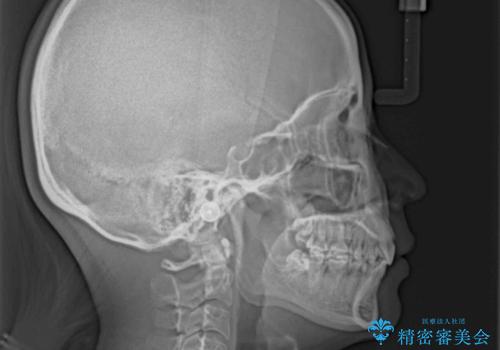

上顎前突 目立たないワイヤー装置での抜歯矯正

- 口元の突出感改善を希望して来院された患者様です。

口元を積極的に引っ込めるために、上下左右の小臼歯計4本を抜歯することとしました。

咬み合わせが深いため、咬み合わせの高さを向上させながら口元を下げることとしました。

左右ともに下顎に対して上顎歯列が前方位にある上顎前突であったので、上顎歯列全体を後方に移動させることで上下咬み合わせを改善し、その上で抜歯矯正により口元の突出感を改善させていきました。